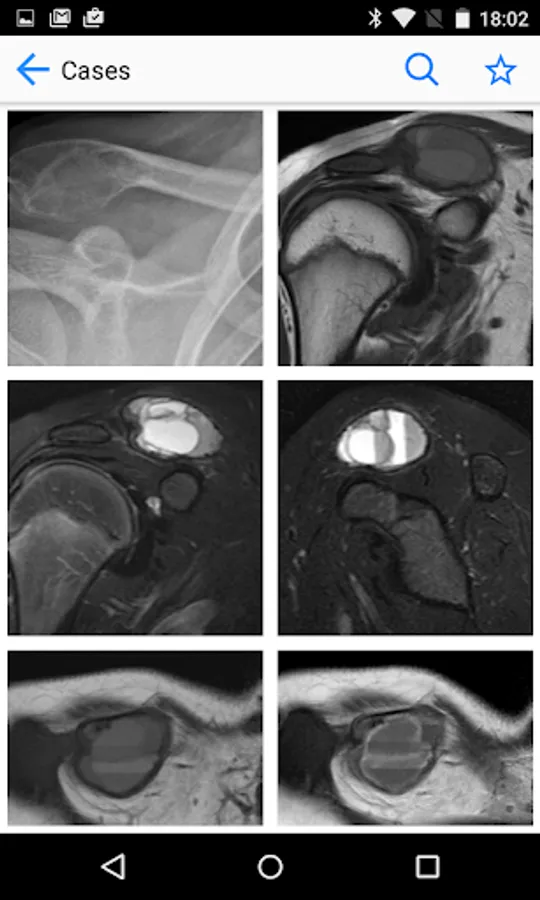

BoSTT brings the user a real experience of frequent and rare, typical and more unusual cases of bone and soft tissue tumours. Each case has a clinical history, high resolution radiology and pathology images, diagnosis, treatment and learning points.